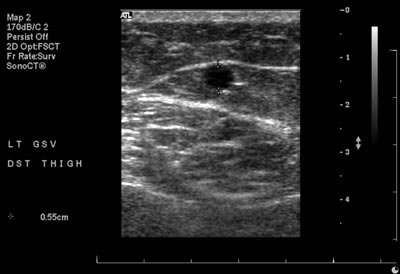

Duplex ultrasound (US)

This is the first-line imaging modality for evaluating vascular access. It allows for vein mapping, which involves assessing the venous anatomy at multiple points along the vessel to determine vein condition, diameter, depth, and tortuosity. It is non-invasive, widely accessible, low cost, and does not require intravenous contrast, which is important for pre-dialysis patients who may be at risk of nephrotoxicity. Duplex US has a high degree of concordance with angiography while avoiding the risks associated with invasive procedures. (Georgiadis et al. 2015) However, duplex US has limitations, such as the inability to visualize central veins adequately.